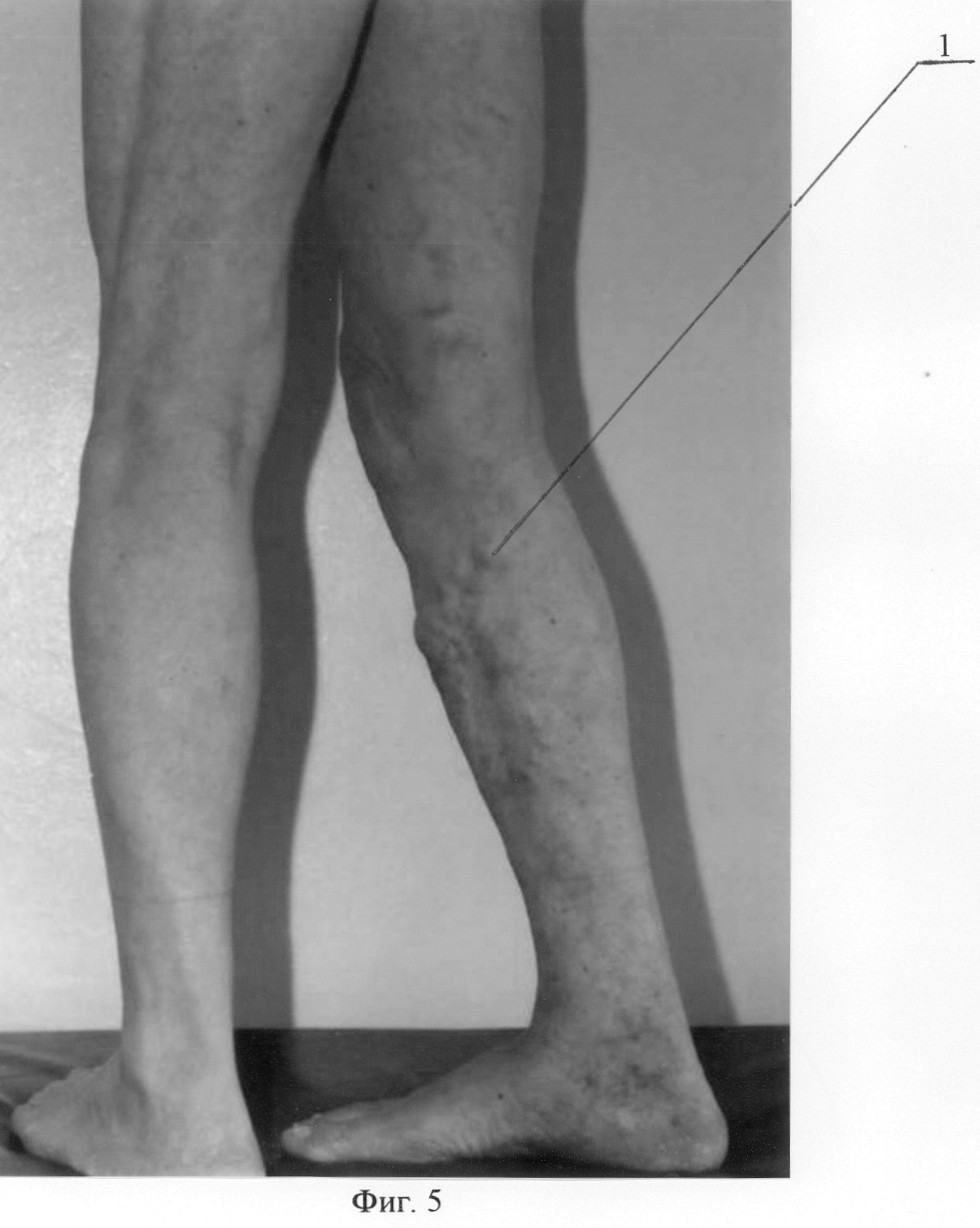

Осмотрен через 1 год. Жалоб не предъявляет. Признаков рецидива варикозной болезни не отмечено. Получен хороший косметический результат. При ультразвуковом дуплексном ангиосканировании признаков патологического сафено-феморального рефлюкса в горизонтальном и вертикальном положениях не выявлено. На фиг.5 изображено состояние правой нижней конечности пациента до лечения, где 1 -варикозно-трансформированная большая подкожная вена; на фиг.6 – состояние правой нижней конечности этого же пациента через 1 год после операции, где 1 – облитерированная на голени большая подкожная вена, 2 – сохраненный ствол большой подкожной вены на бедре.